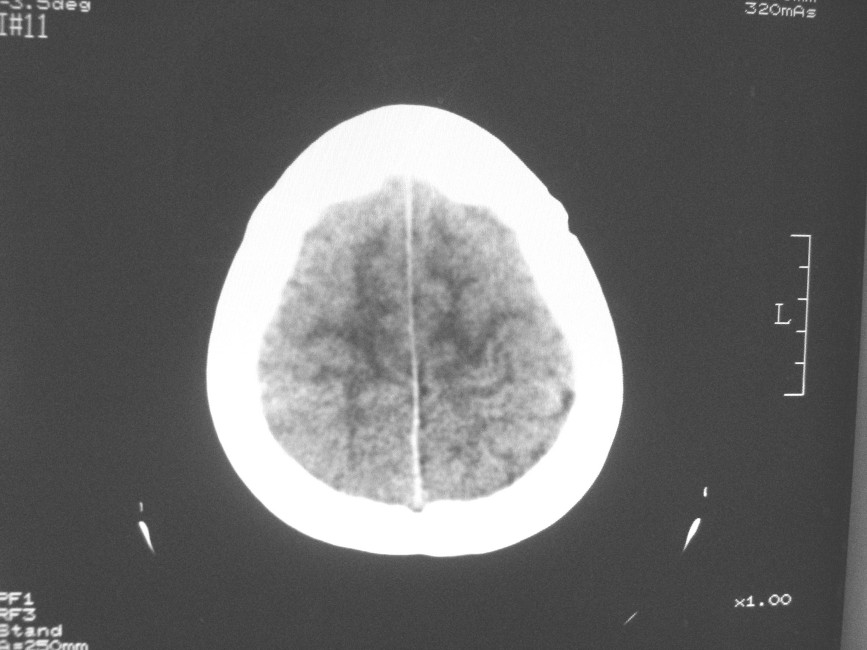

以下是引用zzyy在2008-6-16 10:13:00的发言:[br]两侧脑白质呈对称性密度减低,病儿有发热及脑膜刺激征。考虑急性病毒性脑炎。